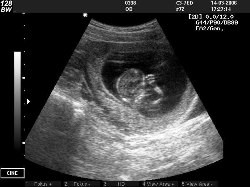

Стоит ли беременным делать УЗИ?

Каждая беременная сталкивается с предложением сделать УЗИ плода. Соглашаться или нет? Врач в женской консультации под давлением спущенных сверху инструкций скажет, что УЗИ совершенно безопасно. Возможно, он даже соврёт, что якобы это исследование является обязательным, и будет шантажировать угрозой не выдать обменную карту или больничный, в случае отказа от УЗИ. Прочитав эту брошюру, вы познакомитесь с иной точкой зрения на УЗИ плода, которая, увы, обычно замалчивается как в СМИ, так и в научно-популярной литературе о беременности и родах. Кроме того, вы узнаете, как защитить свои права при конфликтах с медиками в женской консультации и роддоме...

Так может поосторожничать и делать УЗИ только в крайнем случае? Недаром же ребёнок, «плод», шарахается в сторону от ультразвукового датчика, пытаясь скрыться от него. Это же хорошо видно на дисплее. Всем хочется жить, и ребёнку тоже.

Ультразвуком данный метод называется не потому, что он ультрабезопасен, а потому, что это звуковые волны сверхвысоких частот, не воспринимаемые человеческим слуховым аппаратом. Но еще неизвестно, как их воспринимает эмбрион, по крайней мере, УЗИ изменяет поведение зародыша, особенно на ранних сроках (когда мама еще не чувствует пиночков), что дает повод делать выводы, что всё-таки эти частоты ему небезразличны. Малыш будто бы сопротивляется этой бомбардировке, боится её.

Очень нелепо получается - мы делаем УЗИ, чтобы убедиться в том, что малыш здоров, и тем самым причиняем ему волнения, а возможно и боль... Мое мнение - делать УЗИ не более 3 раз за срок, не ранее 12 недель и только двумерное. Без записи на диск - для экономии времени воздействия.

В более поздние сроки, когда у ребёнка уже полностью сформировано физическое тело, физическое повреждение уже невозможно. Но при этом мы не можем исключить, что ребёнок переживает неприятные эмоции. Есть мнение, что нерождённый ребёнок слышит ультразвук примерно как пушечную канонаду. Я думаю, что в этом есть большая доля истины, т.к. я часто на практике наблюдала, как во время ультразвукового исследования ребёнок ручкой «отталкивает» датчик аппарата, или ручками закрывает себе уши.